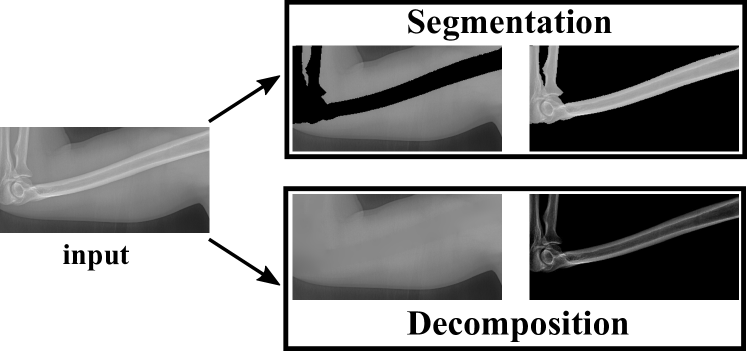

To tackle these problems, we propose to estimate the soft tissue image and bone image simultaneously without losing the linear relationship between image intensity and physical property of the imaging objects. Two examples from our method is shown in Fig. 1. The bone details are enhanced, which is theoretically guaranteed. The details of our method will be explained in later sections.

As shown in the left column of Fig. 1, bones are usually surrounded by the soft tissue. This physical configuration is similar with many natural scenes. One example is the foggy weather, as shown in Fig. 2 (a). The fog can be considered as “soft tissue” (low density) and the buildings can be considered as “bone” (high density).

These limitations motivate us to develop a new and generic mathematical model. Instead of suppressing bones or soft tissue, our model decompose one X-ray image into one soft tissue image and one bone image. These two images have exactly the same imaging domain. Our task is fundamentally different from bone enhancement task and bone suppression task. In fact, our method simultaneously does bone enhancement and bone suppression. As illustrated in Fig. 3, our soft image can be considered as bone suppression while our bone image can be considered as bone enhancement.

Different from the bone enhancement or suppression, we propose to decompose the input X-ray image into one bone image and one soft tissue image. Such task is named as Bone and Soft Tissue Decomposition (BSTD). We construct a new mathematical model that can effectively decompose the soft tissues in X-ray images. Our method decomposes the input X-ray image into background image (soft tissue) and bone image. Be aware the difference between our model and the bone segmentation task. Bone segmentation separates the imaging domain into bone region and background region (without overlap). However, our background and bone images share the same imaging domain (exactly overlapped with the same imaging domain). Such difference is illustrated in Fig. 4.